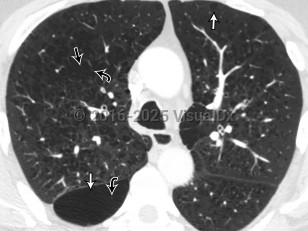

Pulmonary embolismPulmonary embolism

Pulmonary emphysemaPulmonary emphysema